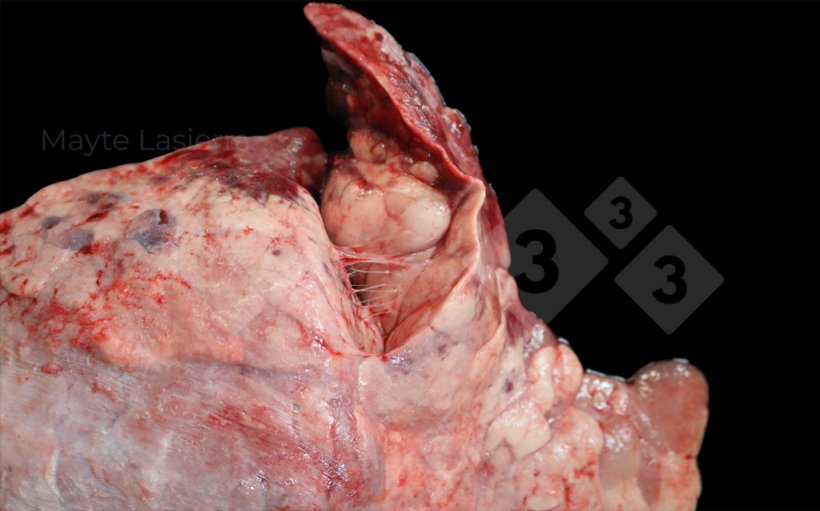

Les pleurésies sont fréquentes et sont des lésions qui touchent la région dorso-caudale du poumon, principalement associées aux formes subaiguës ou chroniques de la pleuropneumonie porcine (APP). Elles se manifestent sous forme de zones blanchâtres sur la plèvre viscérale des lobes diaphragmatiques, qui correspondent à des dépôts de fibrine.

Pleurésie dorsocaudale

Pleurésie dorsocaudale